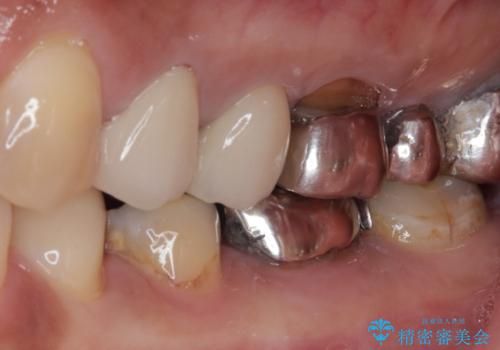

- 銀歯の奥が欠けてしまったとのことで来院された患者様です。

大きな銀歯が装着されており、その下からむし歯が広がっている状態でした。

特に症状はなく、神経組織も健全な状態であったため、むし歯を全て取り切った後にフルジルコニアクラウンにて補綴することとしました。